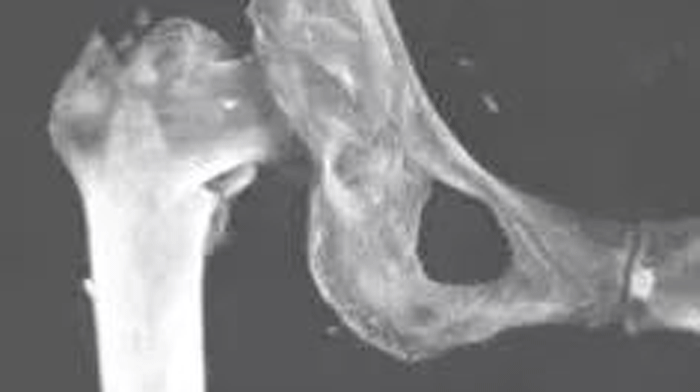

手术中

术前